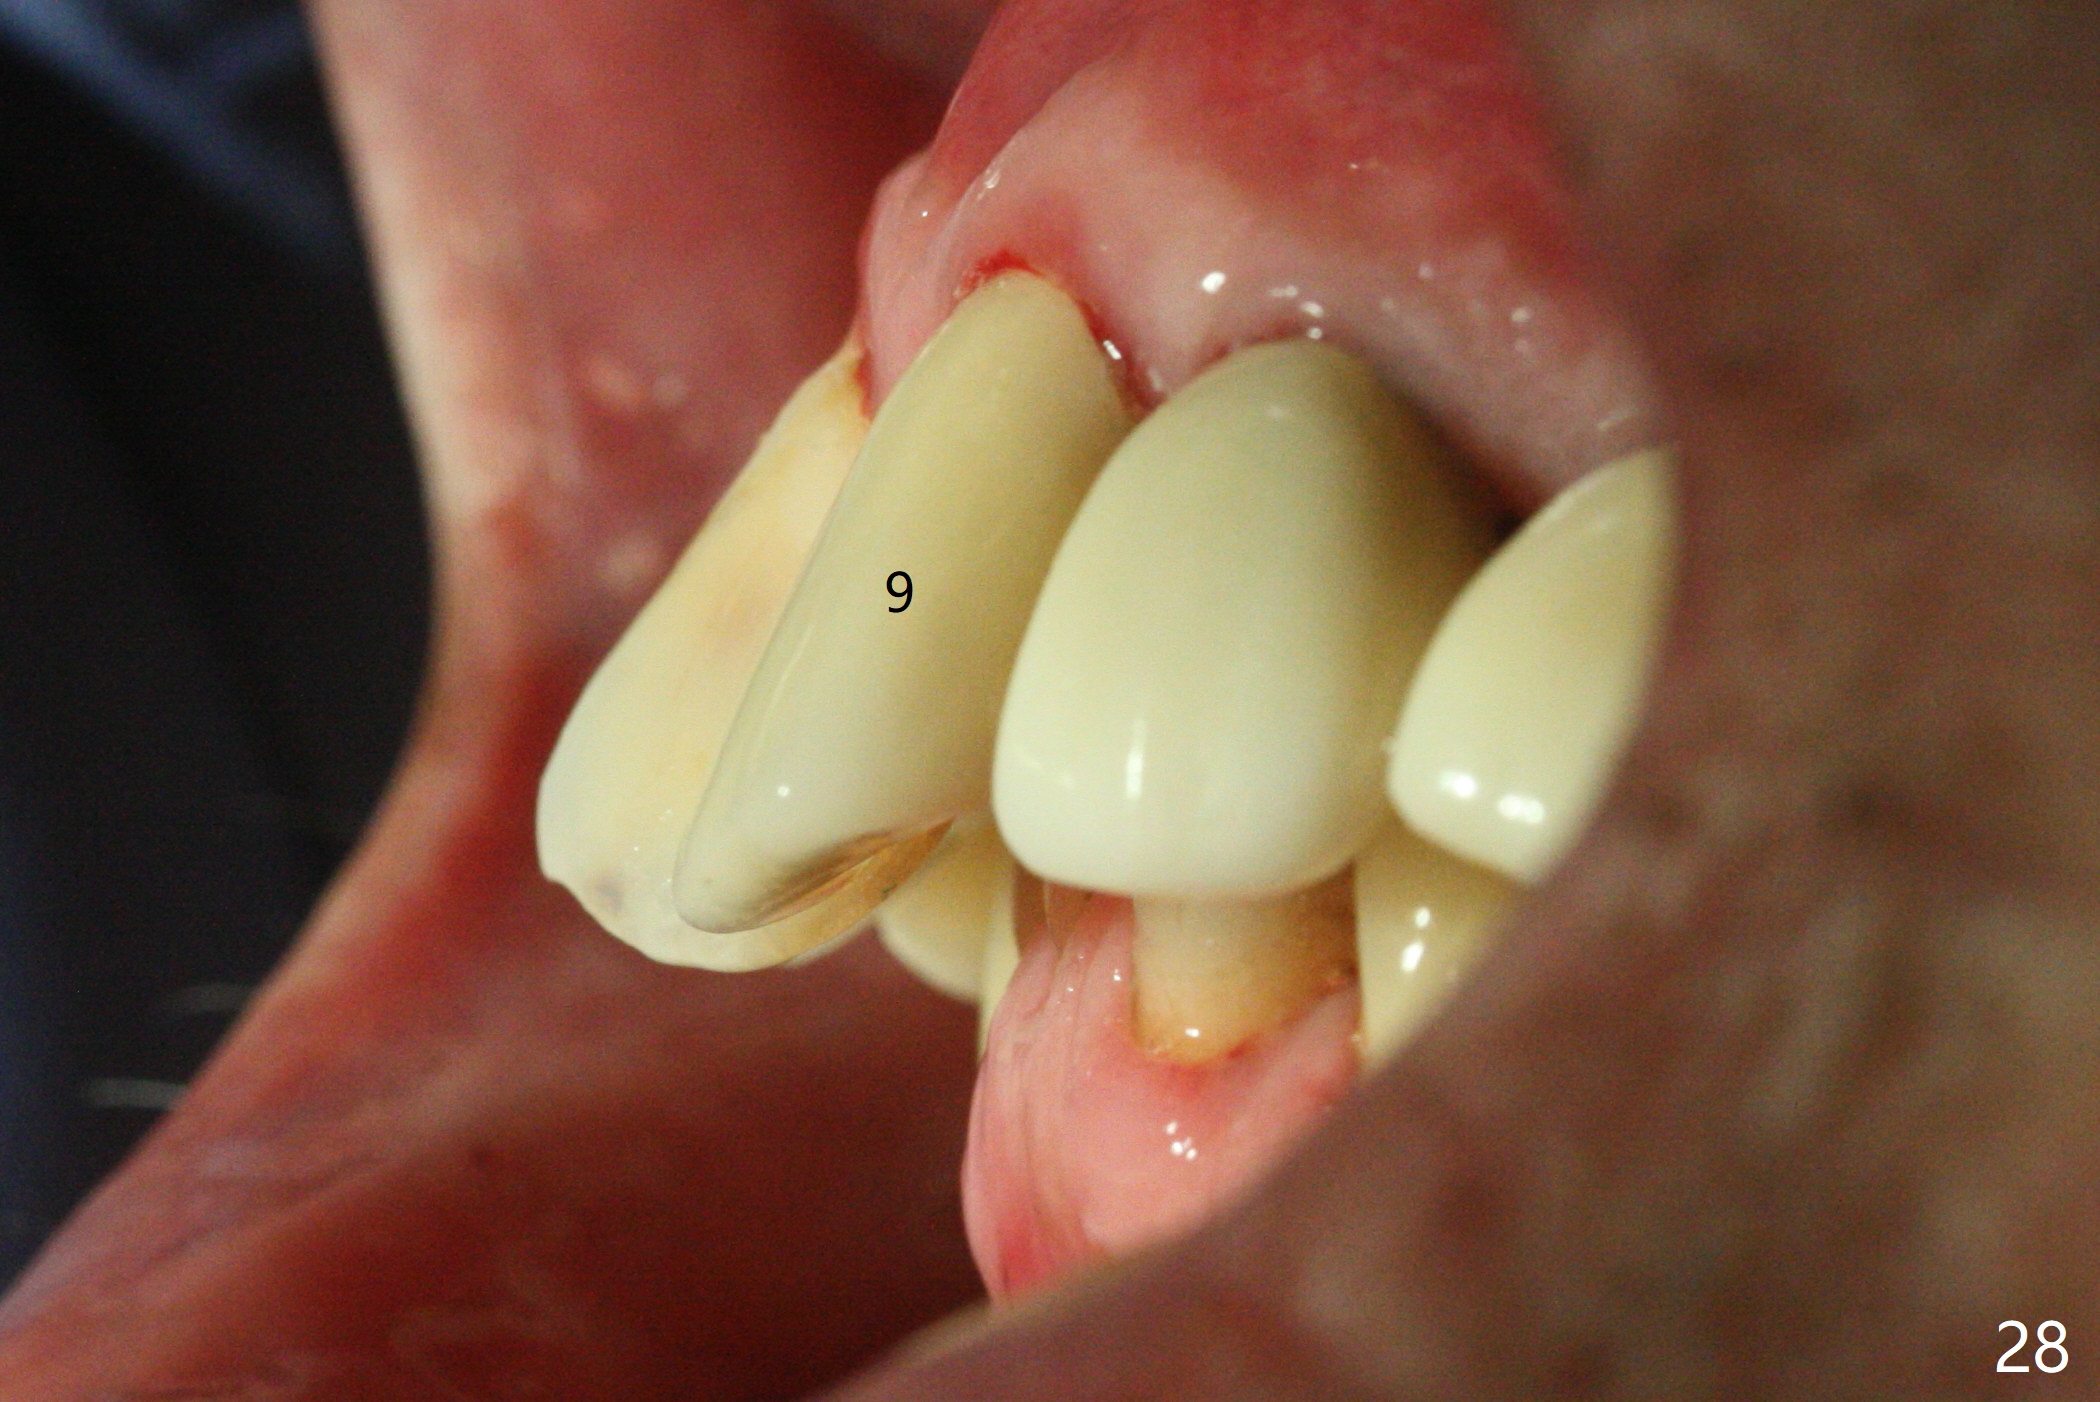

Six months post cementation, the tooth #9 becomes symptomatic. Is it possible that the implant at #10 is too close to the root of #9? It is asymptomatic after pulpotomy, but the tooth fractures equi/supragingivally. Two PAs taken while RCT show osteointegration at #10-12 (Fig.18,19). While the bone density increases at #10 regular implant, there is minimal bone loss around the 1-piece implants 13 months post cementation (18 months postop, Fig.20,21). The gingiva remains healthy 19 months post cementation (Fig.22). 76岁病人突然打电话说一个植牙牙冠松动,其实9号牙(自然牙)折裂,6,10-13号牙植牙好像没有骨质吸收(图二十三至二十五),10-13牙位牙龈健康(图二十六,行使功能五年)。9号牙牙冠重新粘固后,显示前牙深覆合,深覆盖(图二十七,二十八)。如果再次脱落需要植牙,选择一段式有助于植入和修复,因为植体和基台直径小。两段式植牙相对基台直径至少4,或者4.5毫米,前牙修复显得笨重。由于9,10牙根和植体接近,9号牙植体需要偏小而长,3x14或者15毫米(图二十九)。